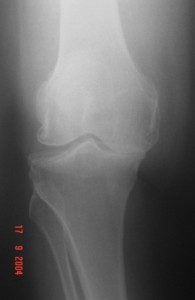

Orta yaş ve üzerindeki diz ağrılarının en sık görülen nedeni “Artrit” halk arasındaki deyişi ile “Kireçlenme”dir. Artritin pek çok nedeni olup bunların arasında en yaygın görülenleri; Osteoartrit, Romatoid Artrit ve Travma Sonrası Artrit dir. Romatoid Artrit ve Posttravmatik Artrit genellikle gençlerde olurken Osteoartrit daha çok orta yaş üzeri kişilerde ve sıklıkla bayanlarda karşımıza çıkan bir hastalıktır. Eklem yüzlerini kaplayan ve yastık görevi yapan kıkırdağın yaş, genetik, yanlış kullanma gibi nedenlerden dolayı yumuşayarak zamanla kaybolması ile seyreden zaman içinde kemikte içe yada dışa eğilme şeklinde deformitelerede neden olabilen bir kıkırdak hastalığıdır.

Radyoloji; Ayakta basarak çekilen grafiler, gerekirse MRI görüntüleriniz, kemik yapınız ve yumuşak dokularınız hakkında bilgi verecektir.